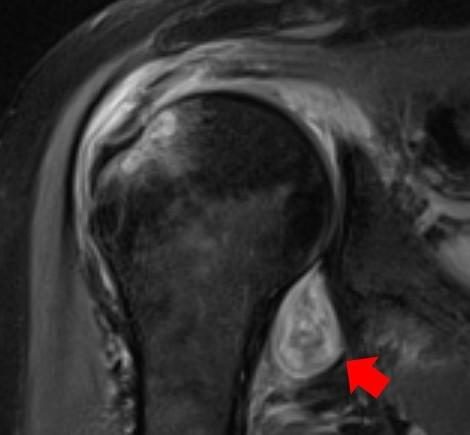

Los especialistas detallan que los hallazgos muestran inflamaciones de tejidos, hematomas e incluso casos de gangrena en los nervios de las articulaciones musculares. “Nos hemos dado cuenta que el COVID-19 puede provocar que el cuerpo se ataque a sí mismo de diferentes maneras, lo que puede producir problemas reumatológicos que requieren un tratamiento de por vida”, añade la especialista.

Pero, por sobre estas utilidades, la más importante es que facilita identificar cómo se ve el daño muscular ocasionado por el COVID-19. “Algunos médicos solicitan radiografías para pacientes con afectaciones como los ‘dedos COVID-19’, pero no había referencias sobre cómo lucen estas afectaciones. ¿Cómo se encuentra algo de lo que no se está seguro cómo se ve?”, resumen los especialistas.